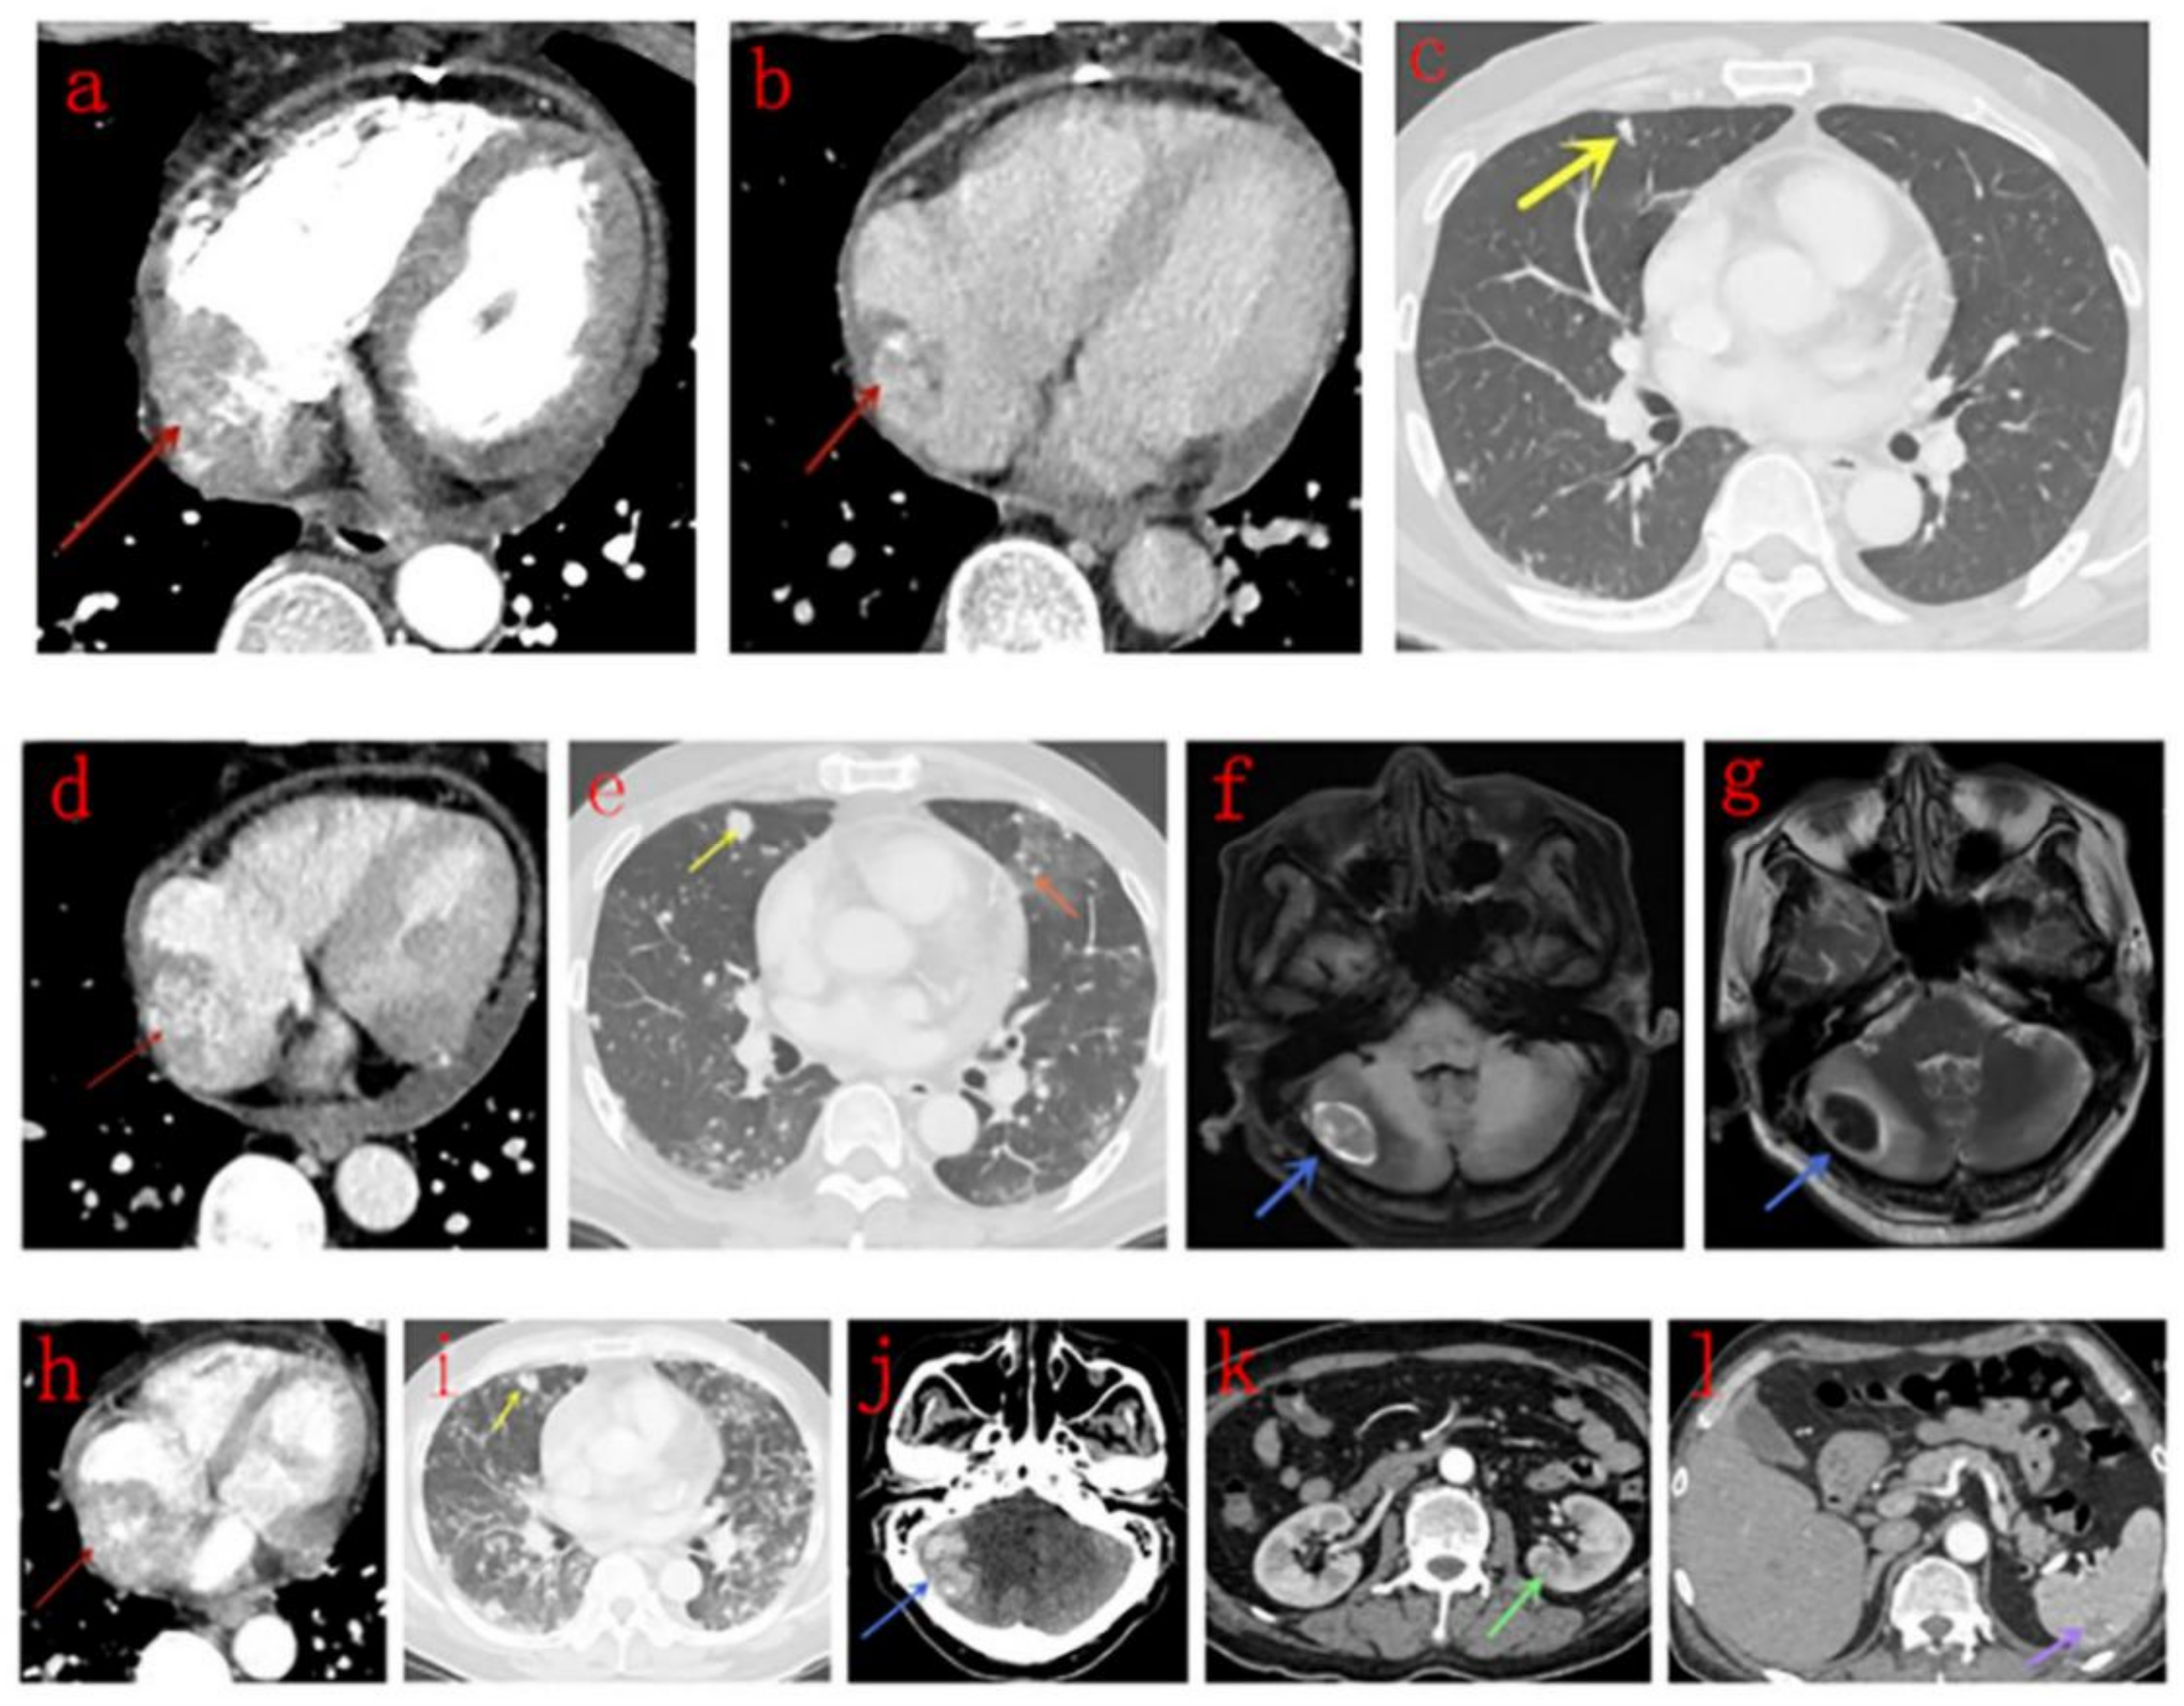

3.2. Imaging Findings

3.3. CT Findings

3.4. MRI Findings

3.5. PET/CT Findings

| Our study | 12 | Masses in the right atrium invading pericardium, RCA, RV, SVC and IVC, presented as homogeneous or inhomogeneous on unenhanced CT scans and heterogeneous centripetal enhancement on enhanced CT scans, The enhancement pattern shows no exact correlation with the differentiation degree of the tumor. Pulmonary metastases with halo sign was common. | Masses in the right atrium invading pericardium, RCA, RV, SVC and IVC, presented as cauliflower-like appearance on T1WI and T2WI, signal void was noticed in a lesion with strong enhancement for arterial phase on CT scan. RA and RV motion was severely impaired. Rim enhancement was noticed in 3 patients and patchy enhancement was noticed in one patient. |